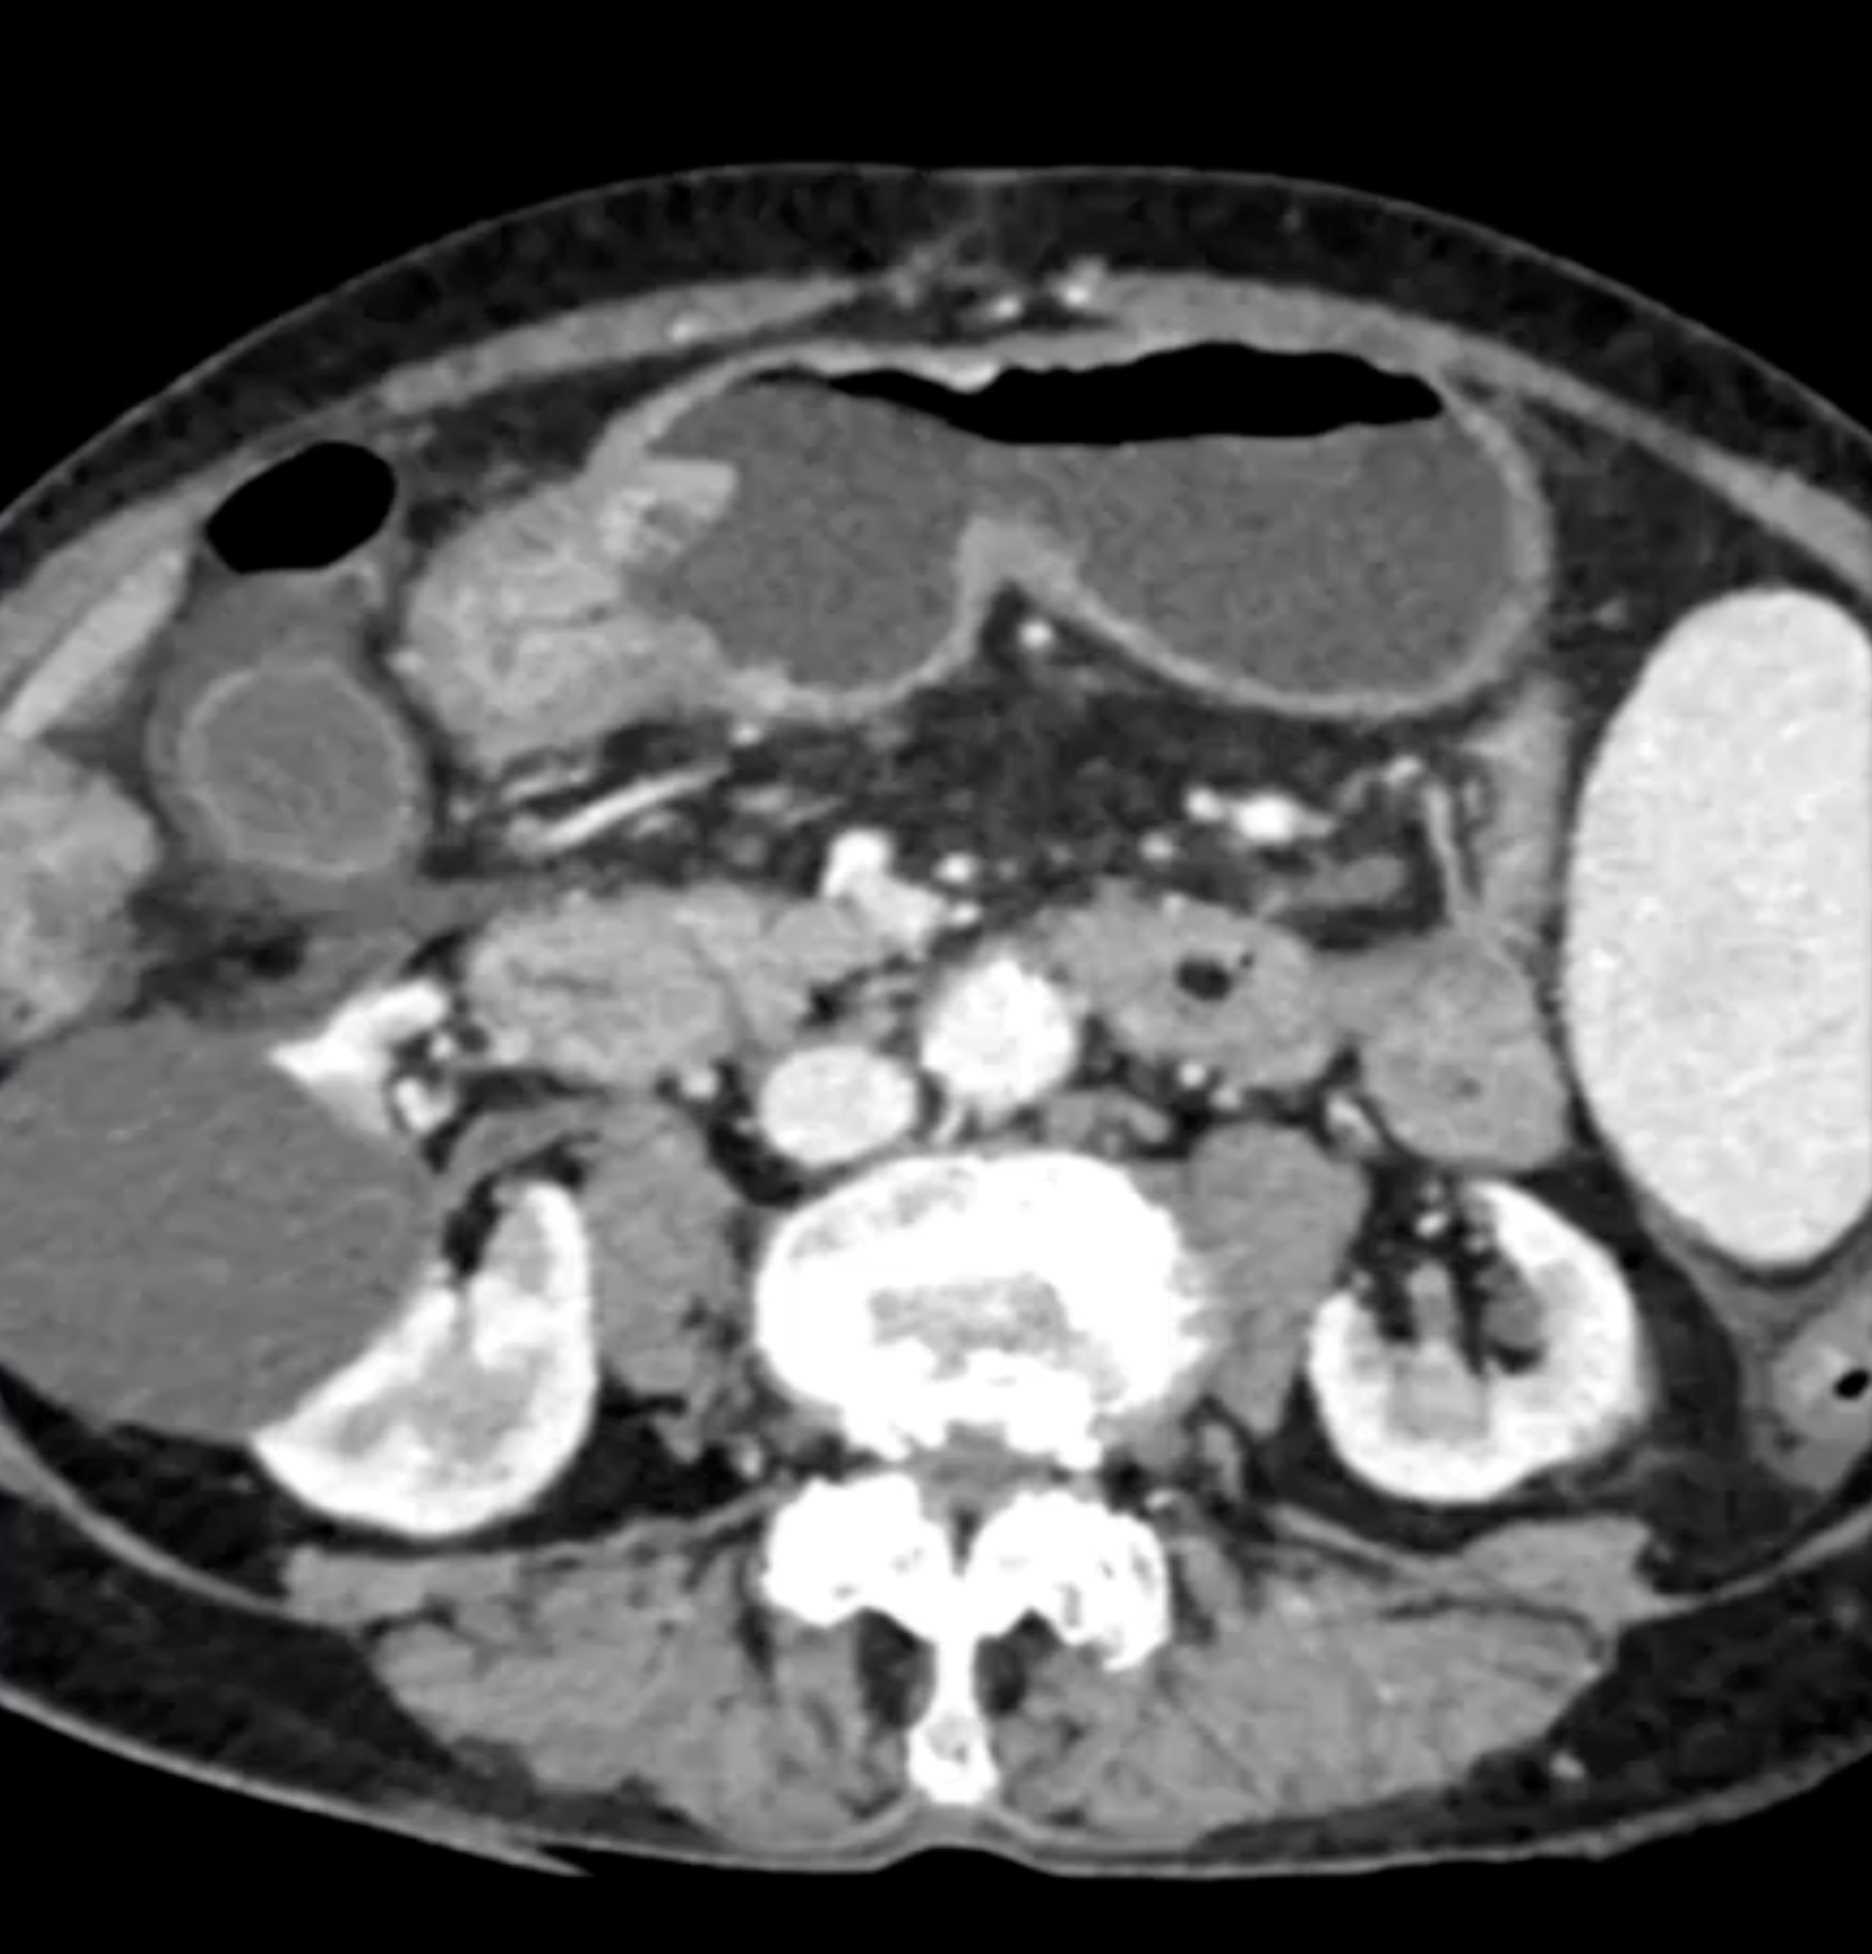

Watermelon Stomach (Gastric Antral Vascular Ectasis)